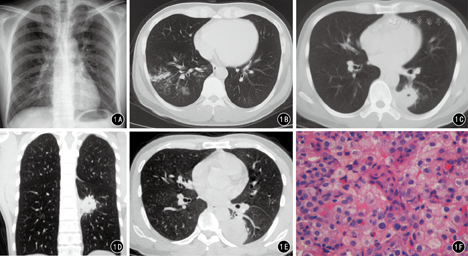

患者男,32岁,无明显原因出现发热2个月,最高体温39 ℃,咳嗽、咳痰,为黄色黏痰。外院按"肺炎"给予"阿奇霉素"治疗2周,体温降至正常,咳嗽、咳痰症状减轻。10 d前再次出现发热,主要于下午及晚间出现,咳白色黏痰,无寒战、盗汗,使用"阿奇霉素"体温控制不佳,于2014年3月5日收治西安交通大学医学院第一附属医院××科。否认肝炎、结核、疟疾等病史;患者久居西安,无疫区、疫情、疫水接触史。体检:体温37.3 ℃,脉搏102次/min,呼吸25次/min,血压113/78 mmHg(1 mmHg=0.133 kPa),神志清楚,精神尚可。实验室检查:白细胞10.46×109/L、中性粒细胞百分比88.01%,肝肾功能、电解质、凝血六项未见异常,结核菌试验弱阳性,红细胞沉降率16 mm/h,C反应蛋白、降钙素原、呼吸道病毒抗体、EB-DNA、CMV-DNA、TB-DNA、斑点试验未见明显异常。X线胸片:两肺纹理增重,右下肺可见淡薄的絮状模糊影(图1A﹚。胸部CT:右肺下叶背段见斑片状高密度渗出影﹙图1B﹚;40天复查CT示右肺下叶背段斑片状高密度影吸收,左肺下叶背段可见约31 mm×32 mm类圆形病灶,其内可见小的空洞影,边界不清,周围可见絮状渗出影,相邻胸膜增厚,胸膜腔少量积液﹙图1C、图1D﹚;2个月后复查CT示示左肺病灶范围增大,约41 mm×52 mm,胸腔积液较前增多。患者俯卧位于CT检查床上,行经皮左肺病灶CT引导下穿刺活检(图1E)。病理检查:肺组织慢性炎伴坏死及纤维组织增生及嗜酸性粒细胞浸润(图1F)。